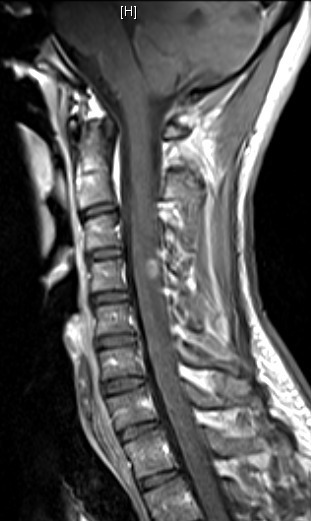

Dissémination spatiale : plusieurs territoires atteints cliniquement, au moins deux territoires atteints en IRM parmi : le territoire périventriculaire, le trajet des nerfs optiques, la région sous/juxta- et intracorticale, la fosse postérieure, la moelle épinière. Particularité des nouveaux critères : prendre en compte les lésions de la fosse postérieure et de la moelle symptomatiques.

Dissémination temporelle : plusieurs poussées cliniques dans le temps, apparition de nouvelles lésions entre les IRM, ou certaines lésions prennent le contraste et pas d’autres sur une même IRM, ou apparition d’une synthèse intrathécale dans le LCS.